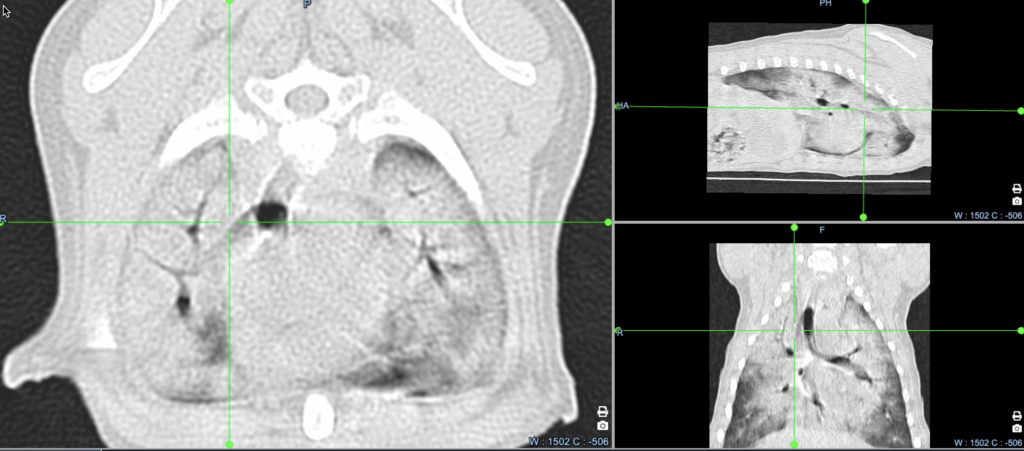

Диагностика. В ОРИТ нашей ветеринарной клиники пациенту была проведена компьютерная томография (КТ), а также был выполнен бронхоальвеолярный лаваж (полученный материал был направлен на цитологическое и бактериологическое исследования). На КТ наблюдалась почти полная консолидация около 90% площади легочной паренхимы (рис. 2).

Была проведена повторная КТ с внутривенным контрастированием, по результатам которой было выявлено значительное увеличение размеров капсул в обоих плечевых (рис. 3, 4), локтевых и тазобедренных суставах, а также в левом коленном суставе по сравнению с данными первоначального КТ-исследования.